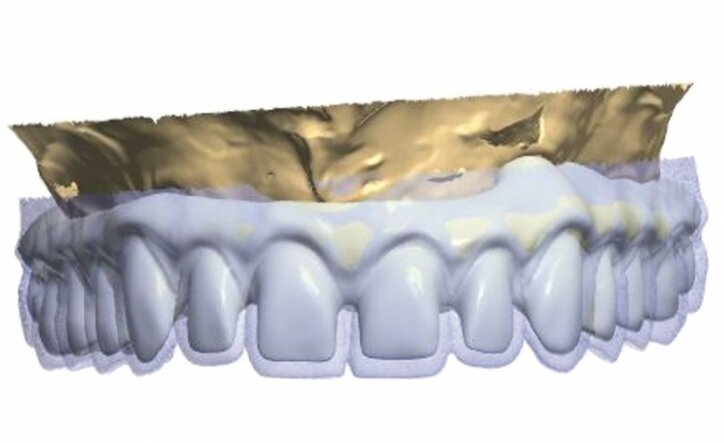

The model was scanned while the abutments were made ready in such a way that they could serve as telescopic crowns, also in the final stage (Fig. 9). Primary and secondary telescopic crowns were designed on the abutments (Figs. 10 & 11) on the assumption that secondary crowns had been made ready twice, that is, for the sake of temporary prosthesis and at the same time for gluing it into the final construction (Figs. 12 & 13). Abutments were mounted on implants by means of Pattern Resin (Figs. 14 & 15) in such a way that the position does not change during mounting.

A temporary skeletal prosthesis, based on four telescopes, shall be placed on such a foundation (Figs. 16 & 17). Primary telescopic crowns were glued last (Fig. 18).

Secondary telescopic crowns, made from acetal by means of the CAD/CAM virtual designing method, were tried on primary crowns (Fig. 19). Figures from 20 to 22 present a macroscopic view of zirconia primary crowns testing and acetal secondary crowns. At that stage, our patient received a temporary prosthesis, while lateral implants remained unloaded (Figs. 23 & 24).

In the second part of the article, we will present the designing process (Figs. 25 and 26) along with the process of manufacture of the final construction made from TRINIA material with glued zirconia crowns as well as veneering by means of pink composite material.